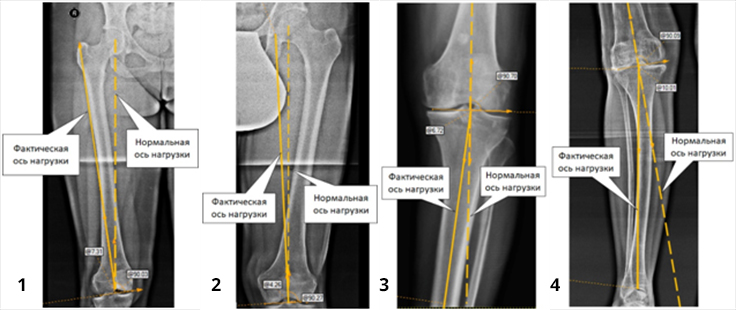

Деформации костей нижних конечностей подразделяют на варусные (1 и 3 фот) и вальгусные (2 и 4 фот). Эти деформации часто сочетаются с ротационными деформациями, когда ось сегмента конечности дополнительно поворачивается или вовнутрь, или наружу. Тогда говорят о сложных деформациях.

Кроме того, что деформации создают косметический дефект («Х-образные ноги», «ноги кавалериста»), они приводят к нарушению распределения нагрузочных сил в суставах, появлению болей в суставах и развитию артрозов. Своевременно выявленные и устраненные установочные деформации являются надежным способом предотвращения развития артрозов голеностопного, коленного и тазобедренного суставов.

У женщины на фоне дисплазии тазобедренного сустава развилась выраженная установочная вальгусная деформация левой голени, которая сопровождалась значительными болями в области коленного и тазобедренного суставов, которые возникали сразу же при начале ходьбы.

В специализированном медучреждении пациентке было предложено выполнить протезирование тазобедренного и коленного суставов, от которых она отказалась.

Мы одномоментно выполнили восстановительные оперативные вмешательства в области голени и тазобедренного сустава. После реабилитационного лечения пациентка полноценно пользуется левой ногой и может длительное время ходить пешком без каких-либо болей в суставах.